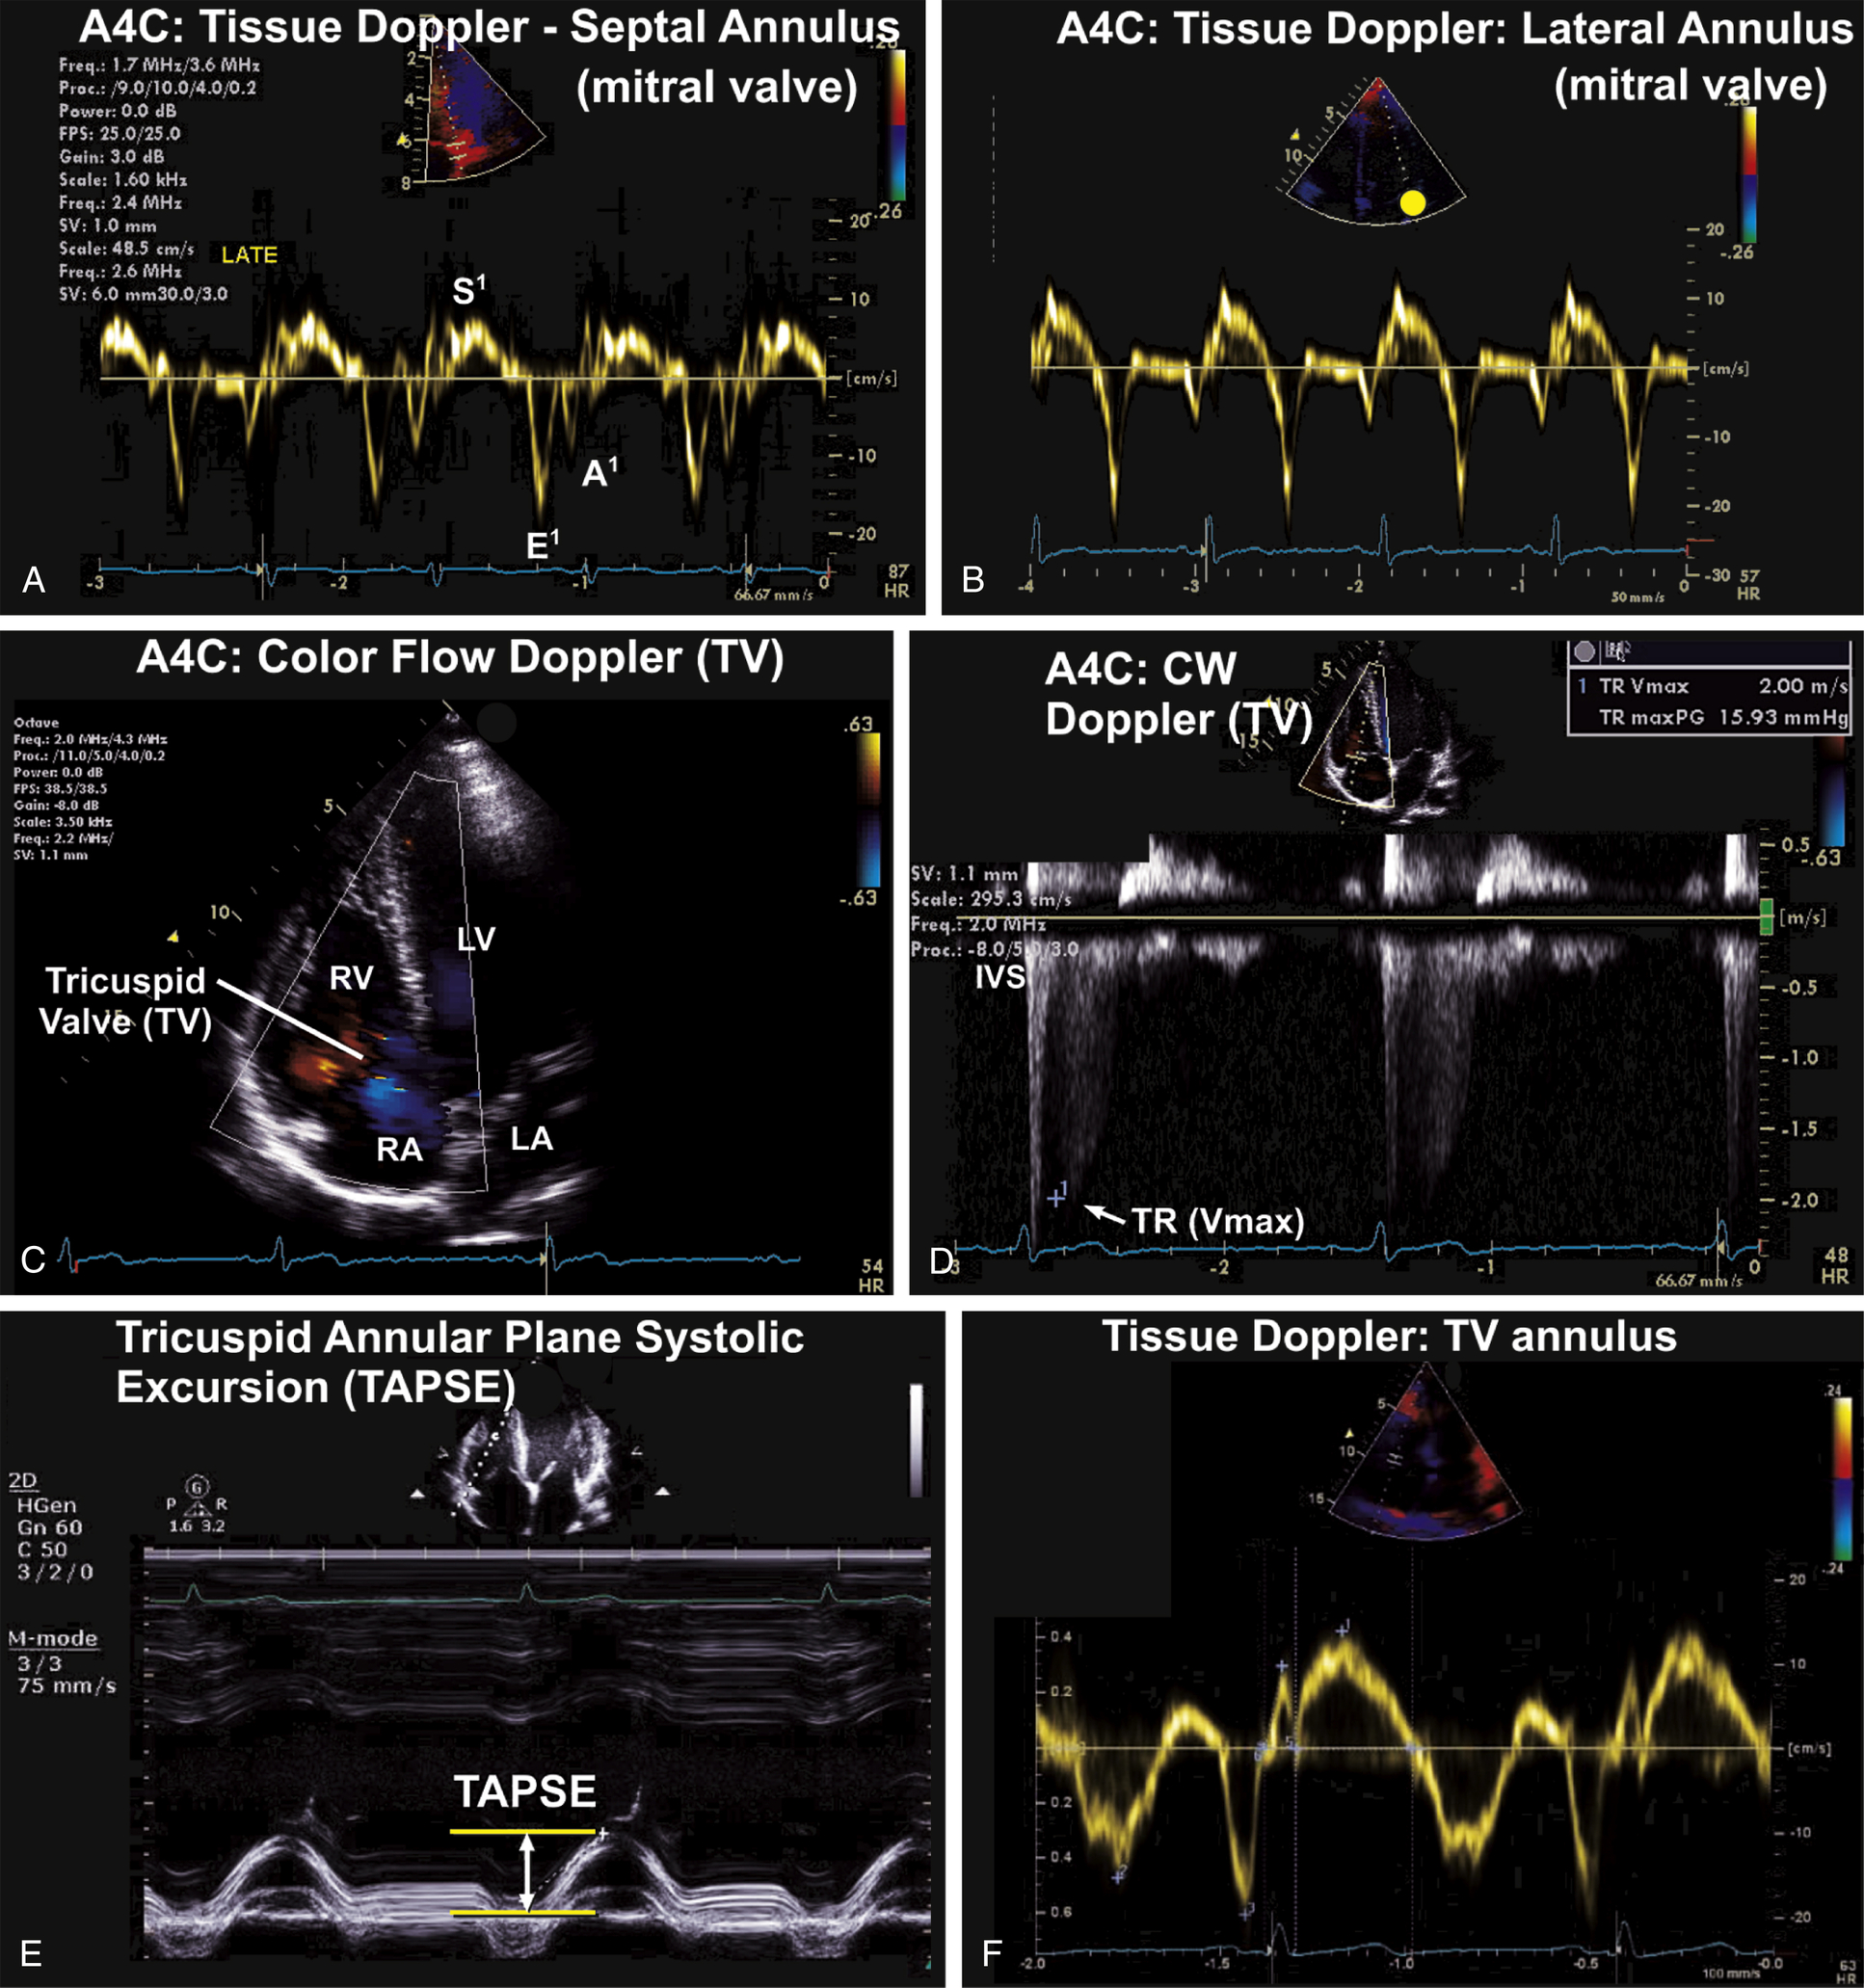

Apical Views (see Figs. 9.5–9.8)

| Transducer Position (Window) | 2d ± M-Mode ± 3d | CFD | Spectral Doppler Pw, Cw | Tissue Doppler Imaging (Tdi) |

| Apical four-chamber (A4C) | 2D image; depth 15–16 cm. 2D Measurement of LA volume- measure LA volume at the end of systole and the shorter length of the LA 3D full-volume (optional) Evaluate RV function on 2D focus RV image. TAPSE (tricuspid annular plane systolic excursion) | CFD to MV for MR, MS CFD the Pulmonary veins, PW of right upper or lower pulmonary vein Color M-Mode flow propagation velocity CFD to TV and CW for TR max velocity. | PW Doppler at the tips of the mitral leaflets for MV inflow CW Doppler of the MV | TDI (PW) of MV annulus (lateral and septal) Color TDI to LV walls TDI of TV annulus |